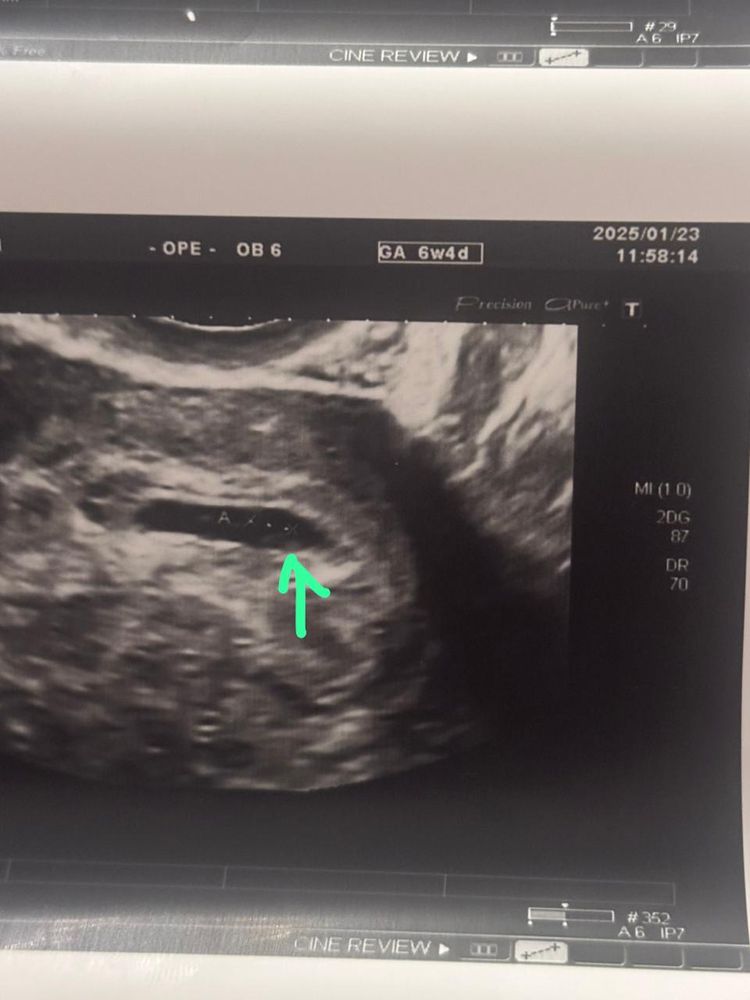

Желточный есть, через 3-5 дней должен быть малышарик

Если уверены в сроке, знаете когда была овуляция, то эмбрион появляется на 30 дпо где-то, это примерно 6 недель с хвостиком. У вас скорее всего он должен появится вот вот или уже есть зачатки) просто яйцо сплющенное и толком не видно

Lilly , в сроке совершенно не уверена, цикл длинный 35 дней примерно, сегодня 47 ДЦ. Да, нашли только ЖМ пока. Врач сказал, что эмбрион только-только появляется, через несколько дней стоит прийти.

Амина Костюк, у меня ровно в 6 недель эмбрион 2,2 с СБ был уже. Может и раньше появился, но пришла я ровно в 6 недель. Но думаю это индивидуально. При условии, если точно знать дату овуляции, то от неё спустя 30 дней все должно быть и эмбрион и СБ

Lilly , по приложению flo сегодня 27 ДПО

Анна, ну как раз 3-4 х дней достаточно будет чтобы все увидеть))